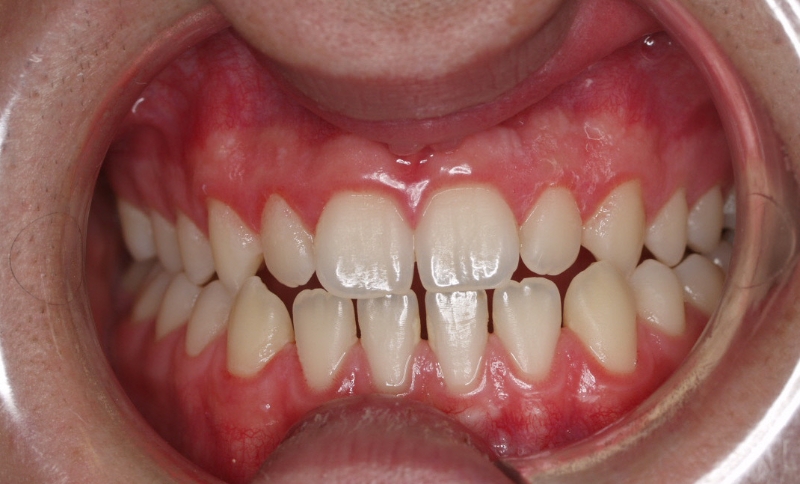

El paciente E.A. acude a nuestra consulta por diastema inferior y ausencia de contactos en los sectores laterales.

1) Arreglamos el problema funcional (lengua baja). Colaboramos con la logopeda Ana Muñoz.

2) Colocamos aparatología fija (brackets Damon) arriba y abajo.